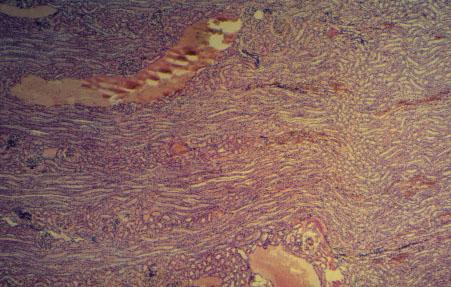

X-4 (4) Slide 85, Human Kidney (H&E). Low power view of the cortex-medullary area. Arcuate veins and medullary rays are seen.